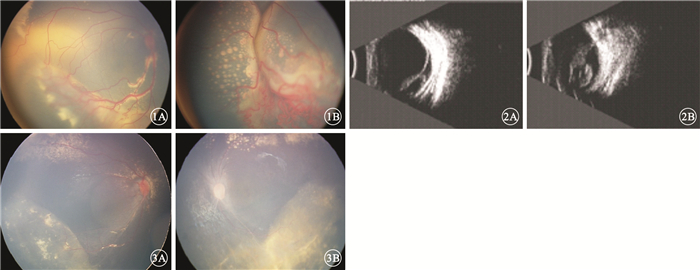

患兒男,1歲。因家長發現患兒視力差不能追物20余天于2013年10月30日來我院眼科就診。患兒發育正常,否認早產及吸氧史、家族相關遺傳病史。全身檢查未見異常。眼科檢查:視力不配合。右眼眼壓17 mmHg(1 mmHg=0.133 kPa),左眼眼壓12 mmHg。雙眼白瞳癥,其余眼前節檢查未見異常。雙眼玻璃體輕度混濁;視網膜可見異常血管增生,顳下方視網膜血管紆曲,末梢血管呈囊樣擴張;視網膜下大量黃白色滲出,視網膜內大量膽固醇結晶。右眼顳側、下方視網膜呈灰白色隆起;左眼視網膜呈灰白色隆起(圖 1)。B型超聲檢查,右眼下方、顳側視網膜脫離,其下可見少量回聲光點;左眼玻璃體腔光帶與視盤相連,視網膜全脫離(圖 2);雙眼未見明確占位病變。外院CT檢查,左眼球較右眼球略大,形態欠規整,右眼球形態尚可。雙眼眼球內可見形態不規則的軟組織密度影,未見明顯鈣化灶;晶狀體形態密度、視神經眼外肌未見明顯異常;肌椎內外間隙未見異常密度影。臨床診斷:(1)雙眼Coats病(右眼3A期,左眼3B期);(2)雙眼滲出性視網膜脫離。明確診斷并完善相關檢查,因患兒眼底視網膜脫離較高,無法激光光凝,征得患兒家屬同意并簽署知情同意書,2013年11月25日給予雙眼玻璃體腔分別注射抗血管內皮生長因子(VEGF)藥物雷珠單抗0.3 mg。此后分別間隔半個月進行3次重復注射治療;2015年1月28日因左眼恢復不理想,給予冷凍、經鞏膜外脈絡膜上腔放液聯合玻璃體腔注射雷珠單抗0.3 mg;3月17日再次雙眼玻璃體腔注射雷珠單抗0.3 mg。5月6日復查,雙眼視網膜灰白色隆起消失;視網膜異常增生的血管明顯消退,仍可見少量黃白色滲出及膽固醇結晶;左眼視盤顏色較淡,其周圍視網膜血管較細(圖 3)。B型超聲檢查,雙眼玻璃體混濁,未見視網膜脫離。治療及隨訪過程中未見與藥物和治療方式相關的眼部和全身并發癥。

雙眼治療前彩色眼底病像。1A.右眼;1B.左眼。視網膜可見異常血管增生,顳下方視網膜血管紆曲,末梢血管呈囊樣擴張;視網膜下可見大量黃白色滲出,視網膜內大量膽固醇結晶??圖 2雙眼治療前B型超聲像。2A.右眼,下方、顳側視網膜脫離,其下可見少量回聲光點;2B.左眼,玻璃體腔內楓葉樣光帶與視盤相連,視網膜全脫離??圖 3雙眼治療后彩色眼底像。3A.右眼;3B.左眼。雙眼視網膜灰白色隆起均已消失,可見少量黃白色滲出及膽固醇結晶;左眼視盤顏色較淡,其周圍視網膜血管較細

雙眼治療前彩色眼底病像。1A.右眼;1B.左眼。視網膜可見異常血管增生,顳下方視網膜血管紆曲,末梢血管呈囊樣擴張;視網膜下可見大量黃白色滲出,視網膜內大量膽固醇結晶??圖 2雙眼治療前B型超聲像。2A.右眼,下方、顳側視網膜脫離,其下可見少量回聲光點;2B.左眼,玻璃體腔內楓葉樣光帶與視盤相連,視網膜全脫離??圖 3雙眼治療后彩色眼底像。3A.右眼;3B.左眼。雙眼視網膜灰白色隆起均已消失,可見少量黃白色滲出及膽固醇結晶;左眼視盤顏色較淡,其周圍視網膜血管較細

患兒男,1歲。因家長發現患兒視力差不能追物20余天于2013年10月30日來我院眼科就診。患兒發育正常,否認早產及吸氧史、家族相關遺傳病史。全身檢查未見異常。眼科檢查:視力不配合。右眼眼壓17 mmHg(1 mmHg=0.133 kPa),左眼眼壓12 mmHg。雙眼白瞳癥,其余眼前節檢查未見異常。雙眼玻璃體輕度混濁;視網膜可見異常血管增生,顳下方視網膜血管紆曲,末梢血管呈囊樣擴張;視網膜下大量黃白色滲出,視網膜內大量膽固醇結晶。右眼顳側、下方視網膜呈灰白色隆起;左眼視網膜呈灰白色隆起(圖 1)。B型超聲檢查,右眼下方、顳側視網膜脫離,其下可見少量回聲光點;左眼玻璃體腔光帶與視盤相連,視網膜全脫離(圖 2);雙眼未見明確占位病變。外院CT檢查,左眼球較右眼球略大,形態欠規整,右眼球形態尚可。雙眼眼球內可見形態不規則的軟組織密度影,未見明顯鈣化灶;晶狀體形態密度、視神經眼外肌未見明顯異常;肌椎內外間隙未見異常密度影。臨床診斷:(1)雙眼Coats病(右眼3A期,左眼3B期);(2)雙眼滲出性視網膜脫離。明確診斷并完善相關檢查,因患兒眼底視網膜脫離較高,無法激光光凝,征得患兒家屬同意并簽署知情同意書,2013年11月25日給予雙眼玻璃體腔分別注射抗血管內皮生長因子(VEGF)藥物雷珠單抗0.3 mg。此后分別間隔半個月進行3次重復注射治療;2015年1月28日因左眼恢復不理想,給予冷凍、經鞏膜外脈絡膜上腔放液聯合玻璃體腔注射雷珠單抗0.3 mg;3月17日再次雙眼玻璃體腔注射雷珠單抗0.3 mg。5月6日復查,雙眼視網膜灰白色隆起消失;視網膜異常增生的血管明顯消退,仍可見少量黃白色滲出及膽固醇結晶;左眼視盤顏色較淡,其周圍視網膜血管較細(圖 3)。B型超聲檢查,雙眼玻璃體混濁,未見視網膜脫離。治療及隨訪過程中未見與藥物和治療方式相關的眼部和全身并發癥。

雙眼治療前彩色眼底病像。1A.右眼;1B.左眼。視網膜可見異常血管增生,顳下方視網膜血管紆曲,末梢血管呈囊樣擴張;視網膜下可見大量黃白色滲出,視網膜內大量膽固醇結晶??圖 2雙眼治療前B型超聲像。2A.右眼,下方、顳側視網膜脫離,其下可見少量回聲光點;2B.左眼,玻璃體腔內楓葉樣光帶與視盤相連,視網膜全脫離??圖 3雙眼治療后彩色眼底像。3A.右眼;3B.左眼。雙眼視網膜灰白色隆起均已消失,可見少量黃白色滲出及膽固醇結晶;左眼視盤顏色較淡,其周圍視網膜血管較細

雙眼治療前彩色眼底病像。1A.右眼;1B.左眼。視網膜可見異常血管增生,顳下方視網膜血管紆曲,末梢血管呈囊樣擴張;視網膜下可見大量黃白色滲出,視網膜內大量膽固醇結晶??圖 2雙眼治療前B型超聲像。2A.右眼,下方、顳側視網膜脫離,其下可見少量回聲光點;2B.左眼,玻璃體腔內楓葉樣光帶與視盤相連,視網膜全脫離??圖 3雙眼治療后彩色眼底像。3A.右眼;3B.左眼。雙眼視網膜灰白色隆起均已消失,可見少量黃白色滲出及膽固醇結晶;左眼視盤顏色較淡,其周圍視網膜血管較細